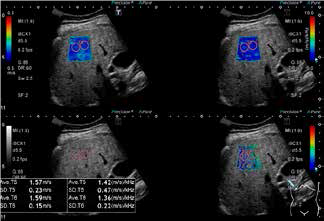

Режим чотирикадрового відображення (Quad View) для SWE доступний на Aplio i-series і дозволяє одночасно спостерігати за картою швидкості/еластичності, картою поширення, В-режимом та дисперсійною картою, яка є новою програмою для оцінки в’язкості печінки (рис. 9). Кількісне визначення швидкості зсувної хвилі, еластичності та дисперсії зсувної хвилі відображаються в режимі Quad View, що полегшує діагностичну ефективність, оскільки діагности можуть виконувати комплексний аналіз, досліджуючи різні характеристики тканин.

Рисунок 9. Еластографія зсувної хвилі в режимі QuadView: 70F, F3 NASH (а) SWE, (b) SWD, (c) В-режим, (d) Карта поширення